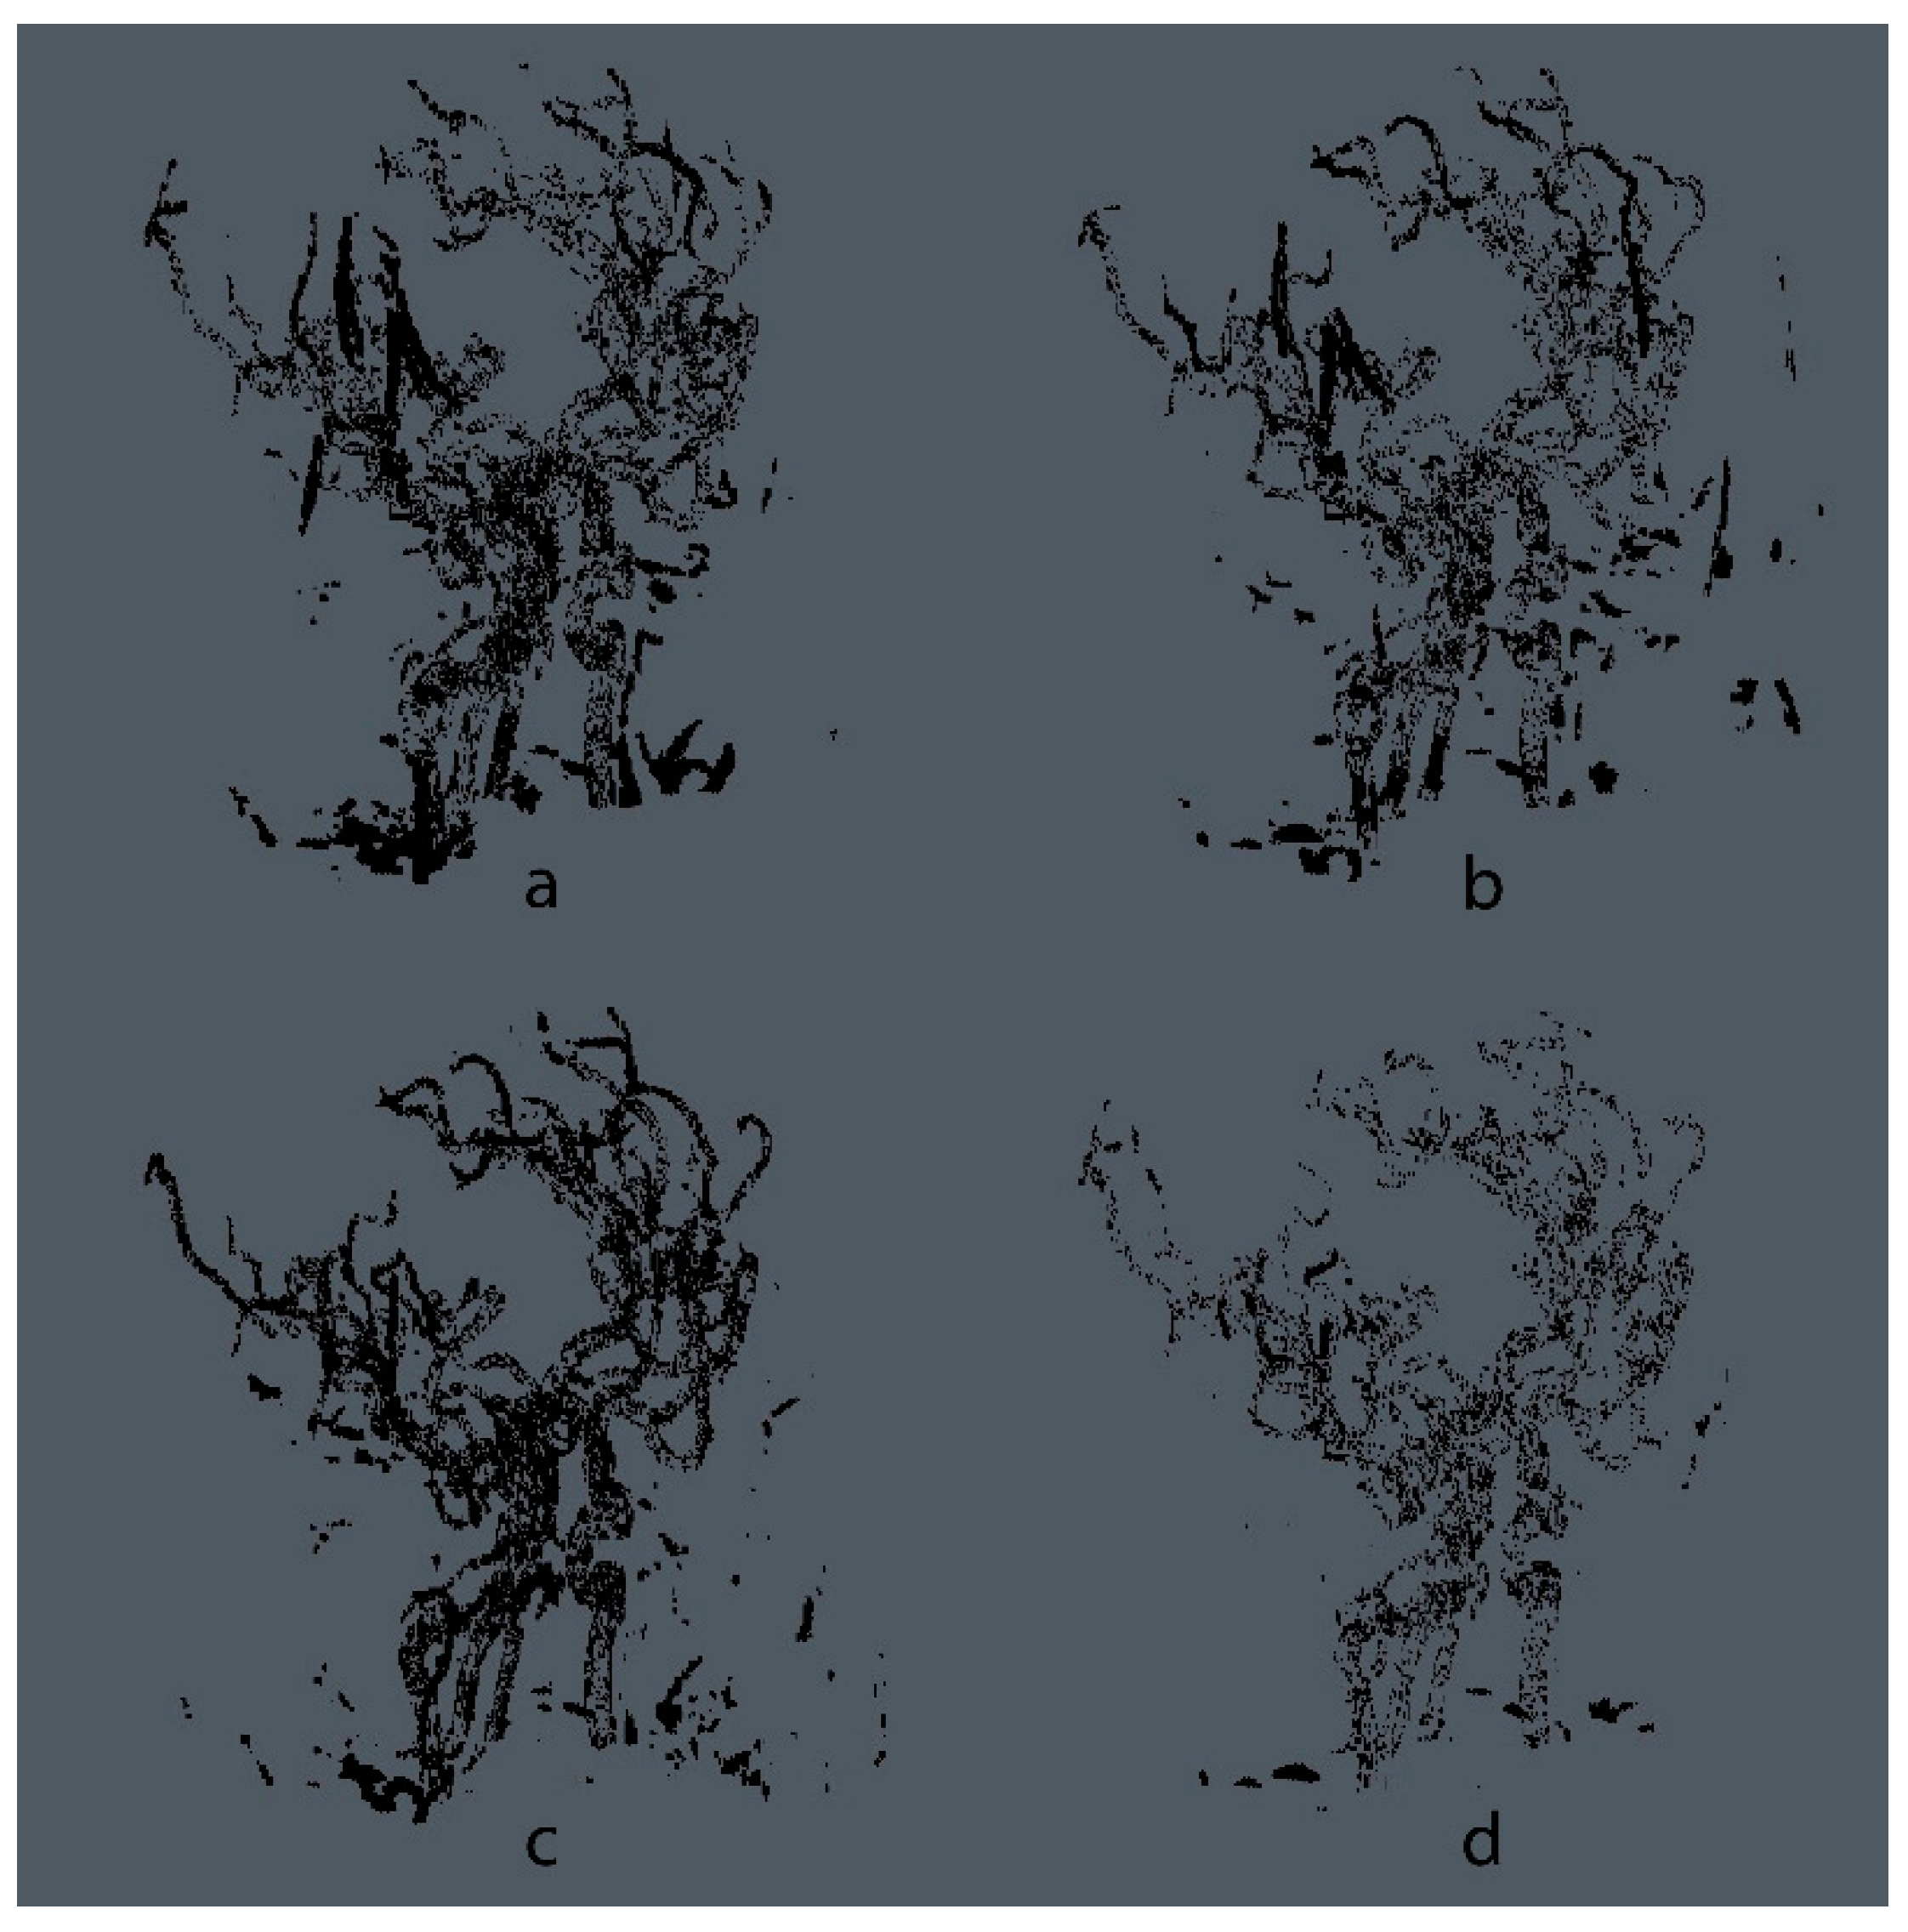

- Additional Experiment Using Microscopy Images